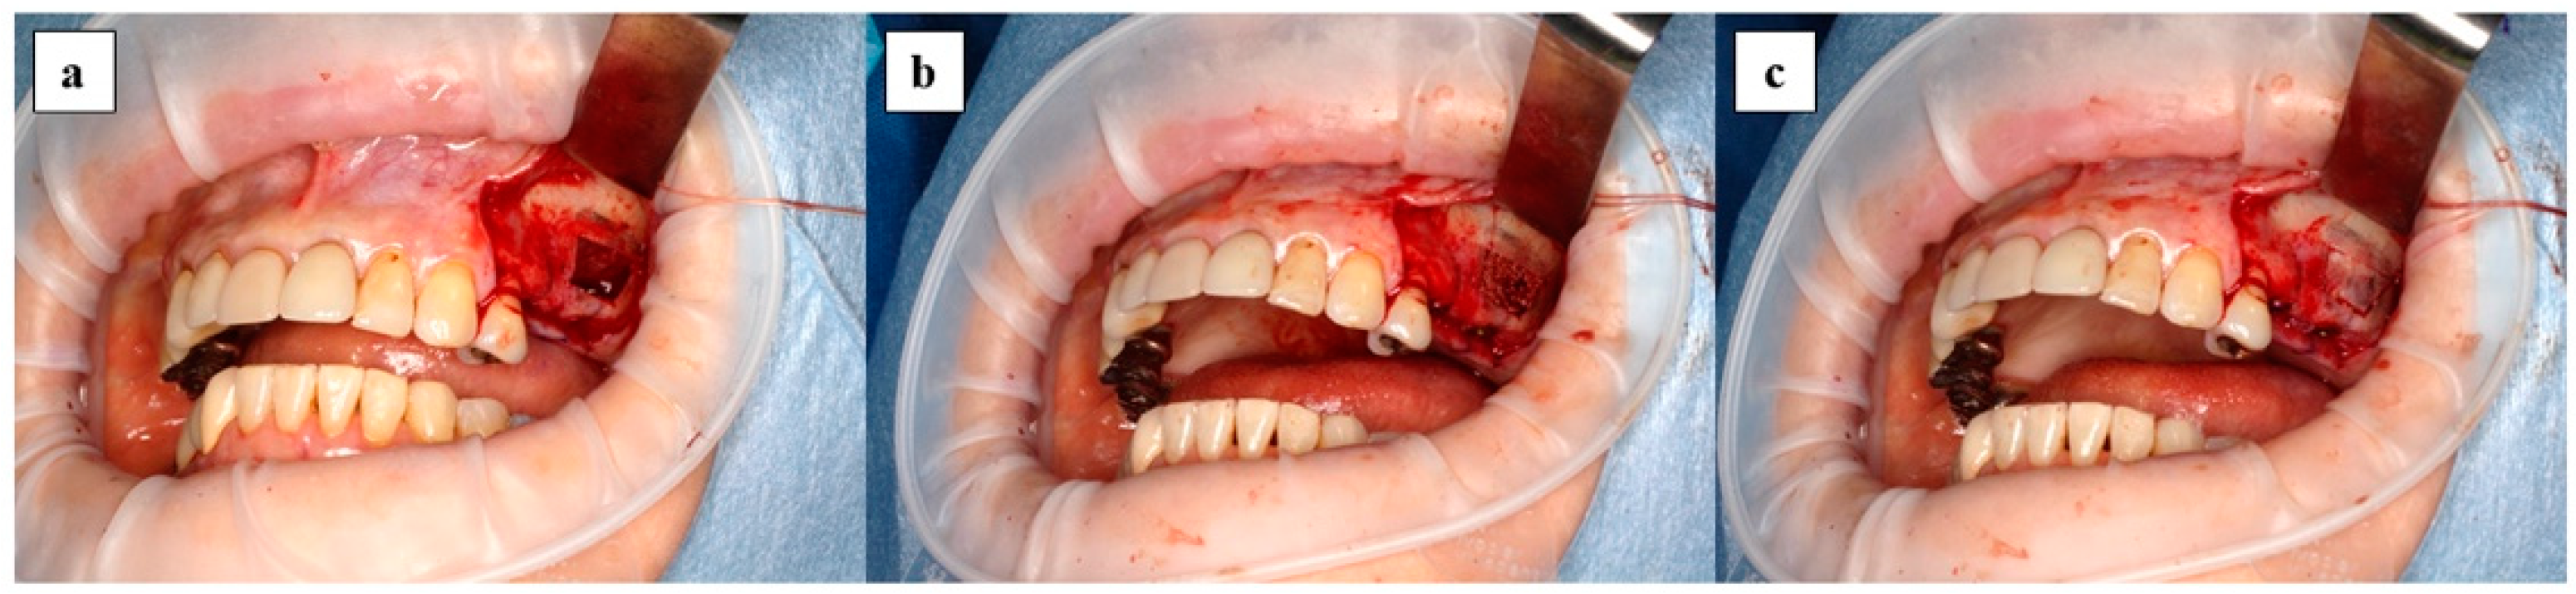

2.4. Surgical Procedure

Maxillary sinus floor augmentation was performed using the lateral window approach as shown in Figure 3. After elevating the mucoperiosteal flap, a bone window was made using a piezoelectric instrument and the maxillary sinus mucous membrane was elevated. After the complex of x3FD-PRP and the bone graft materials were transplanted, the bone window was repositioned and the mucoperiosteal flap was sutured. In case perforation of the maxillary sinus mucosa occurred during surgery, the perforation was closed using absorbent collagen vulnerary covering material when the perforation was less than 5 mm.

Figure 3. Surgical procedure of maxillary sinus floor augmentation is shown: (a) bone window is removed and the maxillary sinus mucous membrane is elevated; (b) complex of x3FD-PRP and bone grafting materials are transplanted; (c) bone window is repositioned.